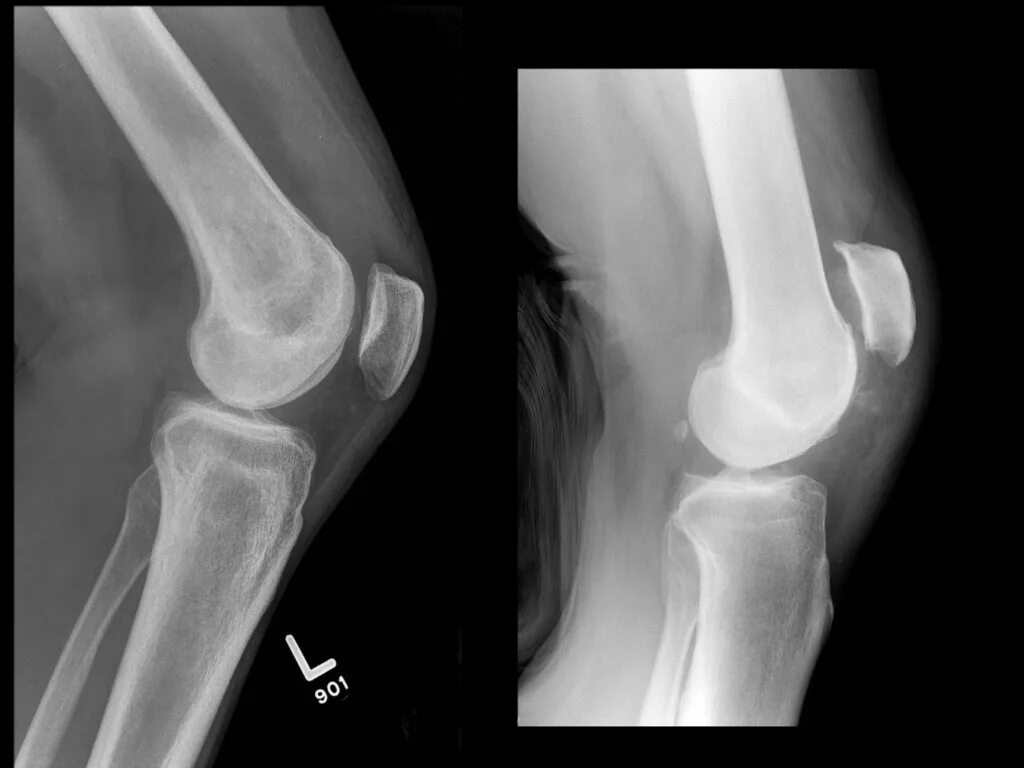

Подвывих сухожилия